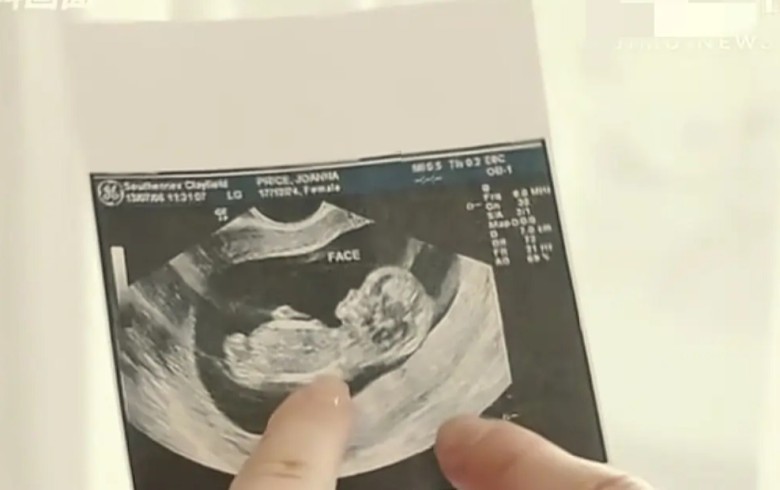

Tại Hà Nam, Trung Quốc, một phụ nữ đến bệnh viện chuyên về hiếm muộn để kiểm tra vì mãi không thể thụ thai. Khi bác sĩ tiến hành siêu âm đầu dò, đầu máy bất ngờ chạm phải một vật cứng. Kiểm tra kỹ, bác sĩ giật mình nhận ra đó chính là… đầu thai nhi.

Bác sĩ điều trị cũng xác nhận chỉ cần sờ nhẹ bên ngoài đã cảm nhận rõ hình hài em bé trong bụng - thai đã khoảng tháng thứ 7.

Bác sĩ đang siêu âm hiếm muộn thì phát hiện bệnh nhân đang bầu 7 tháng.